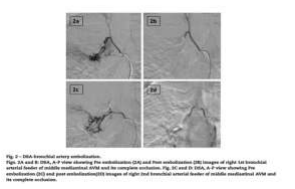

A small component of the meshwork was noted in the subcarinal region. These findings were in favor of AVM. The lesion was enhanced in the aortic phase suggesting its supply from the bronchial artery. So, for better delineation of angioanatomy, digital subtraction angiography (DSA) was considered. A finding of achalasia cardia was noted. DSA of the aorta and selective angiograms of the right intercostobrachial trunk gives rise to the first bronchial artery (Fig. 2A), a second bronchial artery from the aorta (Fig. 2C), left bronchial artery and posterior intercostal arteries confirmed the middle mediastinal AVM supplied by 2 right bronchial arteries and draining into the right superior pulmonary vein (Figs. 2A and C).

The treatment options of surgery and embolization were put forward, out of which the patient gave consent for embolization. Endovascular embolization was done with polyvinyl alcohol particles (PVA-500) and gel foam, after selective cannulation of the first bronchial arterial feeder (Figs. 2A and B) and second bronchial arterial feeder (Figs. 2C and D). With the complete exclusion of the AVM from the circulation at the end of the procedure with no complications. The patient was discharged and is on regular follow-up for 4 years with no recurrence of hemoptysis.